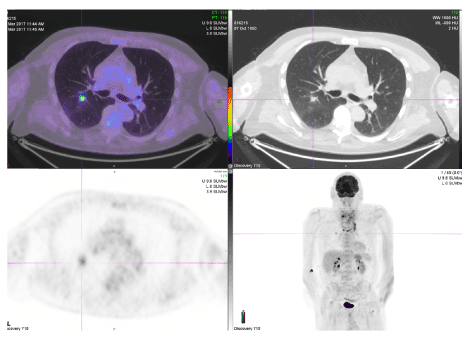

Figure 3. PET-avid nodule within the right lung.

The tissue obtained from the open, incisional biopsy demonstrated a malignant spindle cell tumour, with features favouring leiomyosarcoma. Immunohistochemistry was positive for smooth muscle actin and myosin heavy chain but negative for S100, AE1/3, CAM5.2, TTF1, thyroglobulin, PAX8, EMA, CD34, CD31, SOX10, Desmin and Calcitonin. A staging positron emission tomography (PET) scan was also performed demonstrating locally invasive thyroid malignancy extending into the trachea with multiple pulmonary metastases (Figure 3). After multi-disciplinary oncology discussion, he received local radiation therapy. He elected not to proceed with systemic chemotherapy and received palliative care in the community before passing away approximately four months after diagnosis.